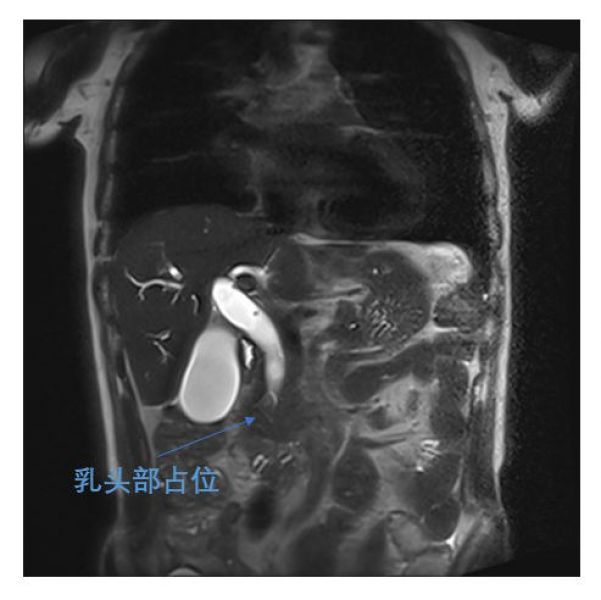

近日,肝胆一科王文儿副主任腹腔镜团队一周内连续完成两例腹腔镜下胰十二指肠切除术(LPD)。这两位手术患者均为70多岁老年男性,1人因发现皮肤巩膜黄染1月就诊发现十二指肠乳头占位,1人因纳差、乏力2月就诊发现乳头占位就诊。肝胆一科团队认真研究及评估两位患者的病情后,决定为他们实施LPD,目前两位患者术后恢复顺利。作为复杂程度很高的普外科四级手术,腹腔镜胰十二指肠切除手术在肝胆一科已作为常规手术开展。

两位患者术前MRI